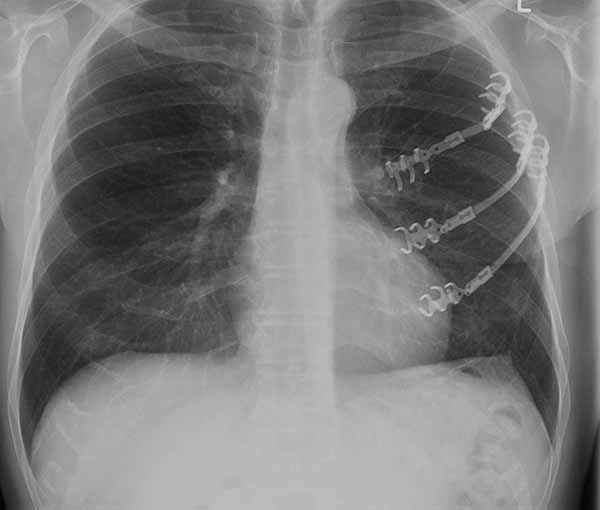

- Chest wall resection for malignancy (Figures 4-5)

![]() |

| Figure 4: Model showing application in chest wall resection. | Figure 5: Postoperative chest x-ray showing the implants |